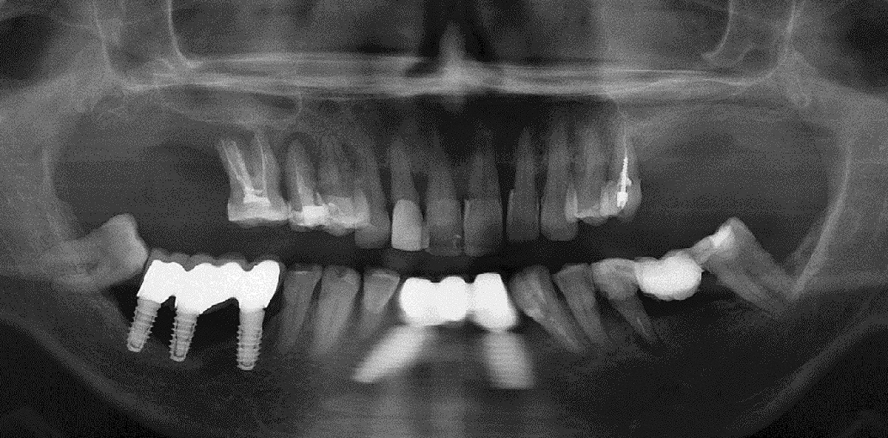

Periimplantitis: Analyse und Hinweise zur Implantatauswahl

Das Wort Periimplantitis endet mit der Endung „-itis“ und lenkt das Gehirn unglücklicherweise in die falsche Richtung. Es wird dazu geneigt, anzunehmen, dass die Ursache der Erkrankung ein bakterieller Befall ist. Ferner wird aus dem Begriff geschlossen, dass als Therapie z. B. Antibiotika eingesetzt werden sollten, um die Infektion als Ursache des Problems zu bekämpfen. Die klinische Wirklichkeit zeigt, dass die Antibiotikatherapie ungeeignet ist, um die Erkrankung einzudämmen oder zu heilen. Folgender Fachbeitrag analysiert in zwei Teilen spezifische Entwicklungen und Besonderheiten des Knochens und arbeitet Ursachen der ­Periimplantitis heraus. Anhand von elf Fragen werden Einzel­aspekte der Knochenphysiologie im Zusammenhang mit Dental­implantaten untersucht.

Die Ursache der Periimplantitis ist nicht in einem Bakterienbefall zu suchen, auch wenn es als Teil der Erscheinung schon bald nach dem ersten Knochenabbau zu einer opportunistischen bakteriellen Besiedlung von rauen Implantatoberflächen kommen kann. Das Auftreten dieser Erkrankung ist in der Literatur mit mehreren Faktoren in Verbindung gebracht worden – je nach Autor und Denkansatz bspw. mit der Belastung des Implantats außerhalb der Längsachse („off-axis load“), mit genereller Überbelastung der krestalen Kortikalis, mit der Unterbelastung des krestalen Knochens, mit generalisierten Erkrankungen des Patienten, mit Plaque in Kombination mit schwerer Überbelastung oder sogar mit dem Rauchen.1–3 Doch selbst eine Korrelation zwischen Periimplantitis und (hormonell bedingter) Osteoporose wurde nicht bestätigt.

Die Ergebnisse wissenschaftlicher Untersuchungen sind divergierend. Viele andere Faktoren wurden und werden diskutiert. Die Kenntnisse über das Problem sind in der Gruppe der privat niedergelassenen Zahnärzte erstaunlich gering. Die Häufigkeit des Auftretens der Periimplantitis und die klinischen Folgen werden im Allgemeinen, von Fachleuten und in der Allgemeinheit unterschätzt. Es wird sogar versucht, durch falsche Publikationen den Eindruck zu erzeugen, dass bestimmte zweiphasige Implantate weniger von dem Problem betroffen sein könnten als andere.4

Typischerweise werden die Patienten nicht oder nicht ausreichend über diese Erkrankung aufgeklärt, die sich einer Behandlung mit herkömmlichen („klassischen“) zweizeitigen Implantaten unterziehen. Die Periimplantitis wird stillschweigend hingenommen, obgleich heute bekannt ist, dass es sehr erfolgreiche orale Implantate gibt, die nicht zu dieser Erscheinung führen.

Die Frage, wie eine Periimplantitis zu behandeln ist und ob es überhaupt eine erfolgreiche Behandlungsmethode gibt, ist eingehend untersucht worden. Problematisch ist, dass der Begriff Periimplantitis weltweit uneinheitlich definiert wird. Erfolgreiche und dauerhaft helfende Behandlungsmethoden wurden in vielen Studien untersucht und nicht gefunden. Unklar ist auch, ob eventuell der Behandlungserfolg nur deswegen erreicht wurde, weil hoch mineralisierte tiefer liegende Knochenareale von der Resorptionsfront erreicht wurden, wonach die Erscheinung aufgrund der verbesserten Knocheneigenschaften in der Tiefe des Kiefers quasi von alleine zum Erliegen kam. Es deutet darauf hin, dass dies die einzige Hoffnung darstellt, um die Krankheit zum Stillstand zu bringen, wenngleich die Entzündung auch in dieser Situation noch persistiert. Häufig ist zu beobachten, dass die progressive Periimplantitis zu raschem Knochenabbau führen kann, wonach die Resorptionsfront „von alleine” stoppt und jahrelang Stabilität auf niedrigem Knochenniveau herrscht. Dies, obgleich die Hebelverhältnisse um die betroffenen Implantate herum grundsätzlich viel ungünstiger sind als vor dem Auftreten der Periimplantitis und dem damit assoziierten Knochenabbau. Diese Beobachtung deutet per se darauf hin, dass es an einer Überbelastung des krestalen Knochens nicht liegen kann. Es ist schon an dieser Stelle darauf hinzuweisen, dass sämtliche Problemlösungsansätze, die Informationen über grundlegende Eigenschaften des Knochens und seine Funktionsweisen außer Acht lassen, niemals zu einem erfolgreichen Behandlungskonzept führen können. Wer am Knochen vorbei behandelt, wird den Knochen schlichtweg gegen sich haben. Heitz-Mayfield und Mombelli haben als Resultat ihrer Auswertung der Literatur festgestellt, dass die Erkrankung in 100 % der behandelten Fälle wieder aufgetreten ist und dabei zwischen 7 % und 93 % der Implantate erneut betroffen waren – dies nach einer erfolgreichen Erstbehandlung.5,6 Esposito et al. kommen in einem umfassenden Review zu dem Schluss, dass die Periimplantitis bei 100 % aller Fälle nach einem Jahr oder später wieder auftritt.7

Die gesamte aktuell verfügbare Literatur zur Behandlung der Periimplantitis bezieht sich auf zweizeitige Implantate mit angerauten Oberflächen, d. h. auf herkömmliche zweiphasige Implantate. Während früher scheinbar die Laserbehandlung überwiegend als Therapie gegen Periimplantitis zum Einsatz kam, scheint heutzutage das mechanische Débridement in Kombination mit einer Antibiotikatherapie der am häufigsten angewendete Therapieversuch zu sein.Es liegen keine Literaturstellen vor, in denen von basalen Implantaten (BOI®, Diskimplant®) im Zusammenhang mit Periimplantitis berichtet wird. Alle glattschaftigen Implantate, d. h. sowohl die lateralen basalen Implantate als auch schraubbare basale Implantate (z. B. BCS®, Bikortikalschraube), bieten keinerlei Retentionsflächen für Bakterien. Daher wurde das Auftreten einer Periimplantitis bei BCS- und BOI-Implantaten nie in der Literatur beschrieben. Nach alledem, was bisher beobachtet wurde, scheinen diese Implantate nicht von der Erscheinung betroffen zu sein. Weltweit berichten diejenigen Implantologen, die diese Implantate ständig und langjährig einsetzten, dass sie das Auftreten dieser Erkrankung nicht beobachten. Auch die Durchsicht der gesamten bekannten Literatur auf diesem Gebiet – welches früher als „Basalosseointegration” bezeichnet wurde – deutet darauf hin.8